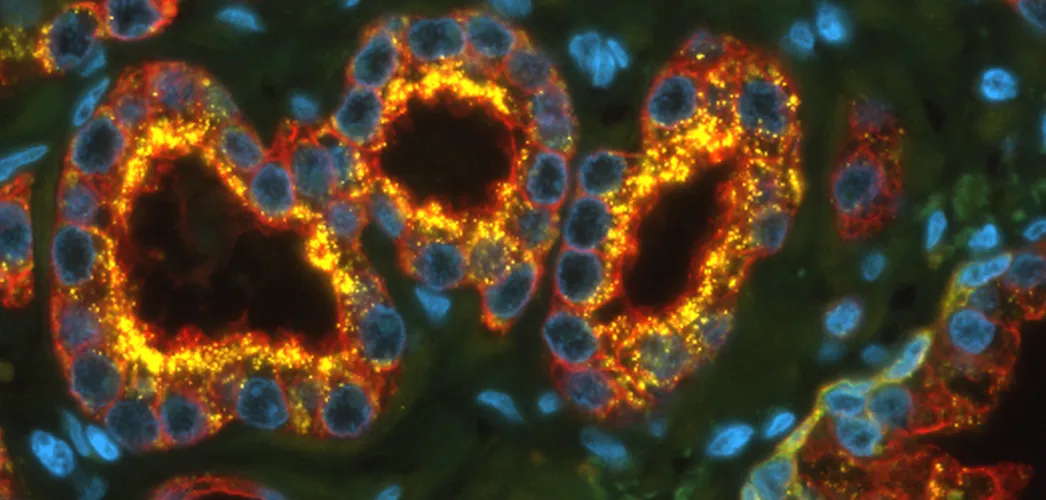

Multiplexing Techniques as Useful Tools for High-Content Phenotyping

Multiplexing enables high-content phenotyping by analyzing multiple markers in a single tissue section. Combined with TissueFAXS CHROMA and StrataQuest Apps, it delivers detailed insights into tumor microenvironments and complex cellular interactions.